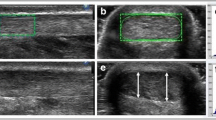

All US images were analyzed with an open-source image processing program (ImageJ 1.48v; National Institutes of Health, USA). From the three obtained images only the image which showed the least pressure application was selected and digitized on three consecutive days. The tendon CSA was manually outlined (excluding the paratenon) and calculated by the software (Fig. 4a). The mean value of three measurements of the same image was defined as distal or proximal CSA, respectively.

The subject was positioned supine with knees fully extended and the ankle joint was carefully placed with small weight bags in the head coil. Sagittal images were recorded and used to adjust the FOV at a right angle to the AT path at the level of both spherical markers. Finally, 12 transversal images for each measurement position (distal, proximal) were obtained. Two out of 24 images, which contained the spherical markers with their largest diameter (Fig. 4b), were exported and the CSA was measured on three consecutive days with ImageJ as follows: At first, the images were converted (32 bit grayscale) and calibrated.

Subsequently, an adjustable threshold cut-off method was used to identify the AT boundaries (Fig. 4b). The selection of the appropriate threshold cut-off was standardized for both examiners by the following criterion: The threshold was adjusted until the smallest CSA representing the natural appearance of the AT CSA (nearly oval shape with round boundaries) was visible. The outlined CSA was further calculated automatically by the software and the mean value of three measurements of the same image was defined as CSA.